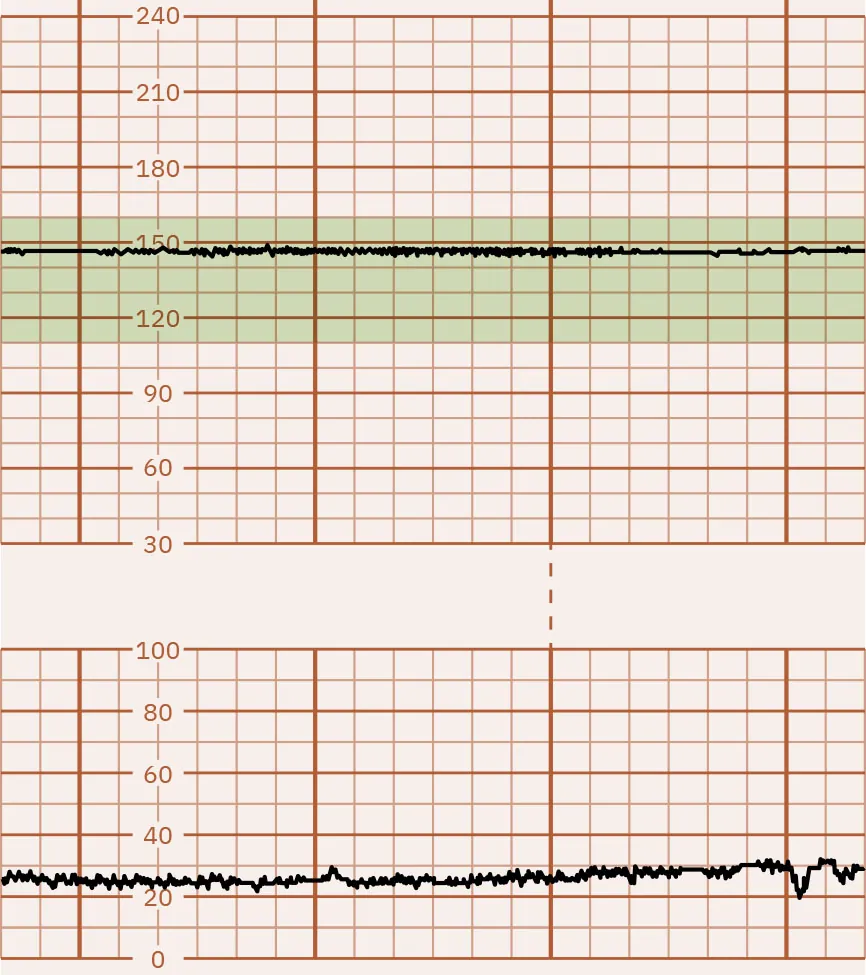

Absent FHR Variability

A lack of FHR baseline fluctuation is considered absent FHR variability. Absent variability is most often a sign of a severely compromised fetus. Figure 16.7 illustrates absent FHR variability. Fetal compromise can be the result of poor oxygenation leading to metabolic acidosis. Fetal acidemia depresses the CNS, causing a loss of FHR variability. Acidemia of the pregnant person can also cause absent FHR variability. Changes in the FHR variability from moderate to minimal or to absent may indicate fetal stress and require further investigation by the nurse and notification of the health-care provider.

Fetal heart rate reading indicating absent variability.

Figure 16.7 Monitor Tracing That Indicates Absent FHR Variability This monitor tracing shows absent FHR variability, essentially a straight line. (attribution: Copyright Rice University, OpenStax, under CC BY 4.0 license)